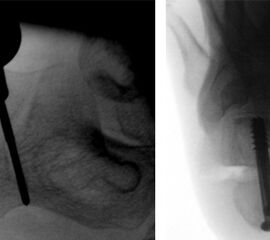

Auch bei der OP des linken Fußes steht der Bildverstärker links des OP-Tisches. Analog zum Vorgehen rechts wird der Zentralstrahl für die seitliche Aufnahme im 90° Winkel zur Kalkaneusachse ausgerichtet. Das nicht zu operierende Bein ist etwas abgesenkt. Für die axiale Aufnahme wird der Bildverstärker maximal nach kaudal gekippt, der Zentralstrahl ist auf die Ferse zentriert und verläuft weitgehend parallel zur Osteotomieebene (Abb. 9a und b)

Der Operateur steht hinter dem linken Fuß. Die Maschine für das Fräsensystem steht am Fußende. Der Monitor steht für den Operateur gut sichtbar auf der linken Seite neben dem Bildverstärker (Abb. 9c und d).